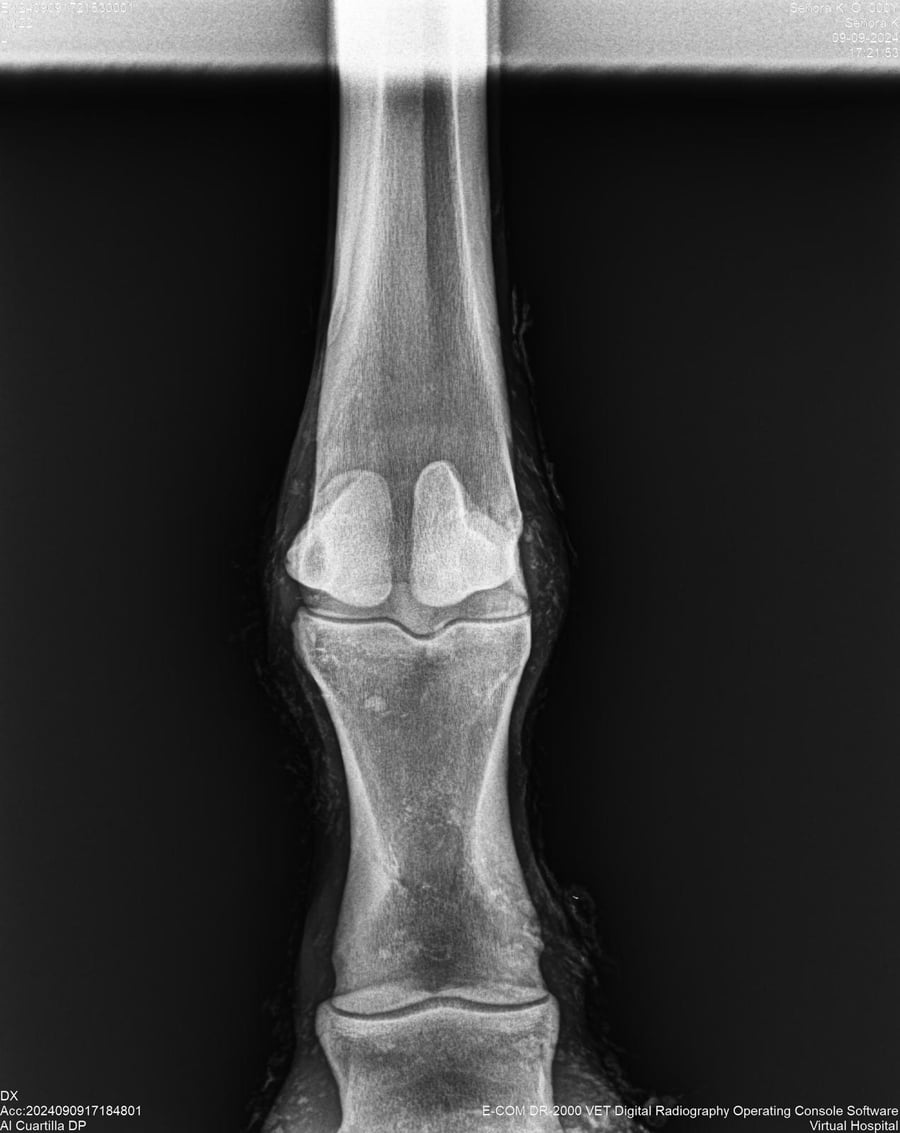

LOTE 44, SEÑORA K

Identificador: #291147-

Generacion 2022